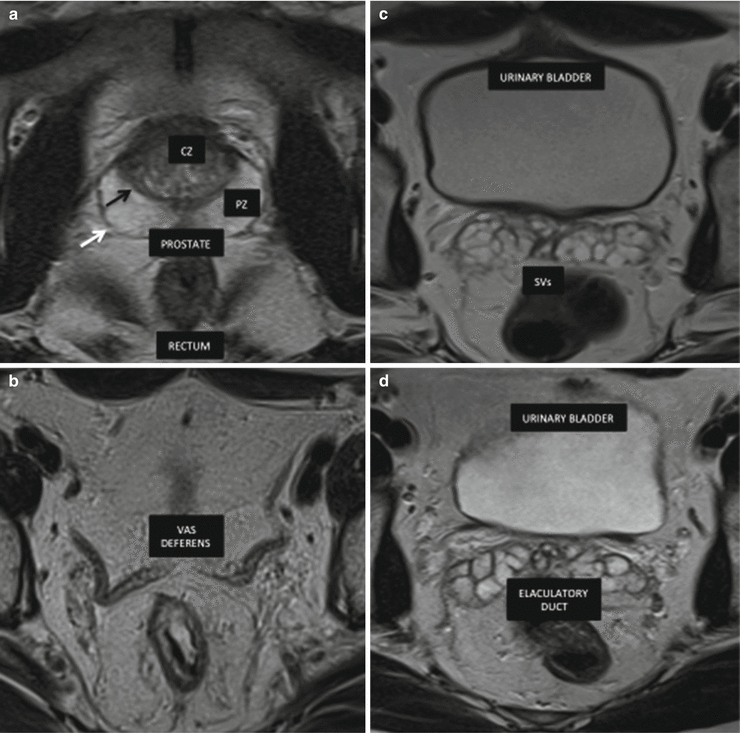

Fig. 9.5

Anatomy of the prostate, seminal vesicles and vas deferens. MRI modality of choice due to its soft tissue contrast and multi-planar capabilities and no ionizing radiation. (a) Axial T2-weighted MR image shows peripheral zone (PZ) of the prostate with homogeneous hyperitensity, and the central zone (CZ) with hypointensity of the prostate capsule (white arrow) and the surgical capsule (black arrow). (b) The vas deferens is seen as a tubular structure medial to the seminal and displays low T2 signal intensity. (c) Axial T2-weighted MR image shows the normal hyperintensity lobulated pattern of the seminal vesicles. (d) Axial T2-weighted MR image shows the anatomy of the ejaculatory duct (ED)